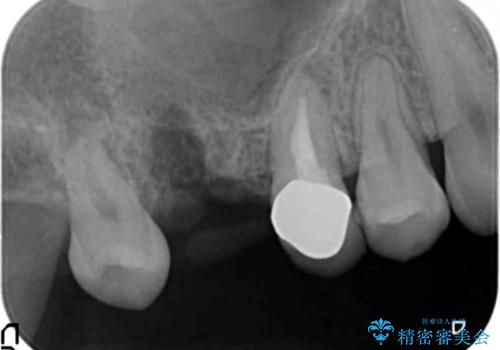

奥歯2本(右上76)はう蝕が深く保存不可能な状態であったため、やむなく抜歯しました。

インプラントも入れ歯も抵抗があるとのご相談により、自家歯牙移植を提案しました。

使っていない親知らず(右上8)を右上7抜歯窩に移植し、支台歯としてブリッジによる補綴治療を行いました。